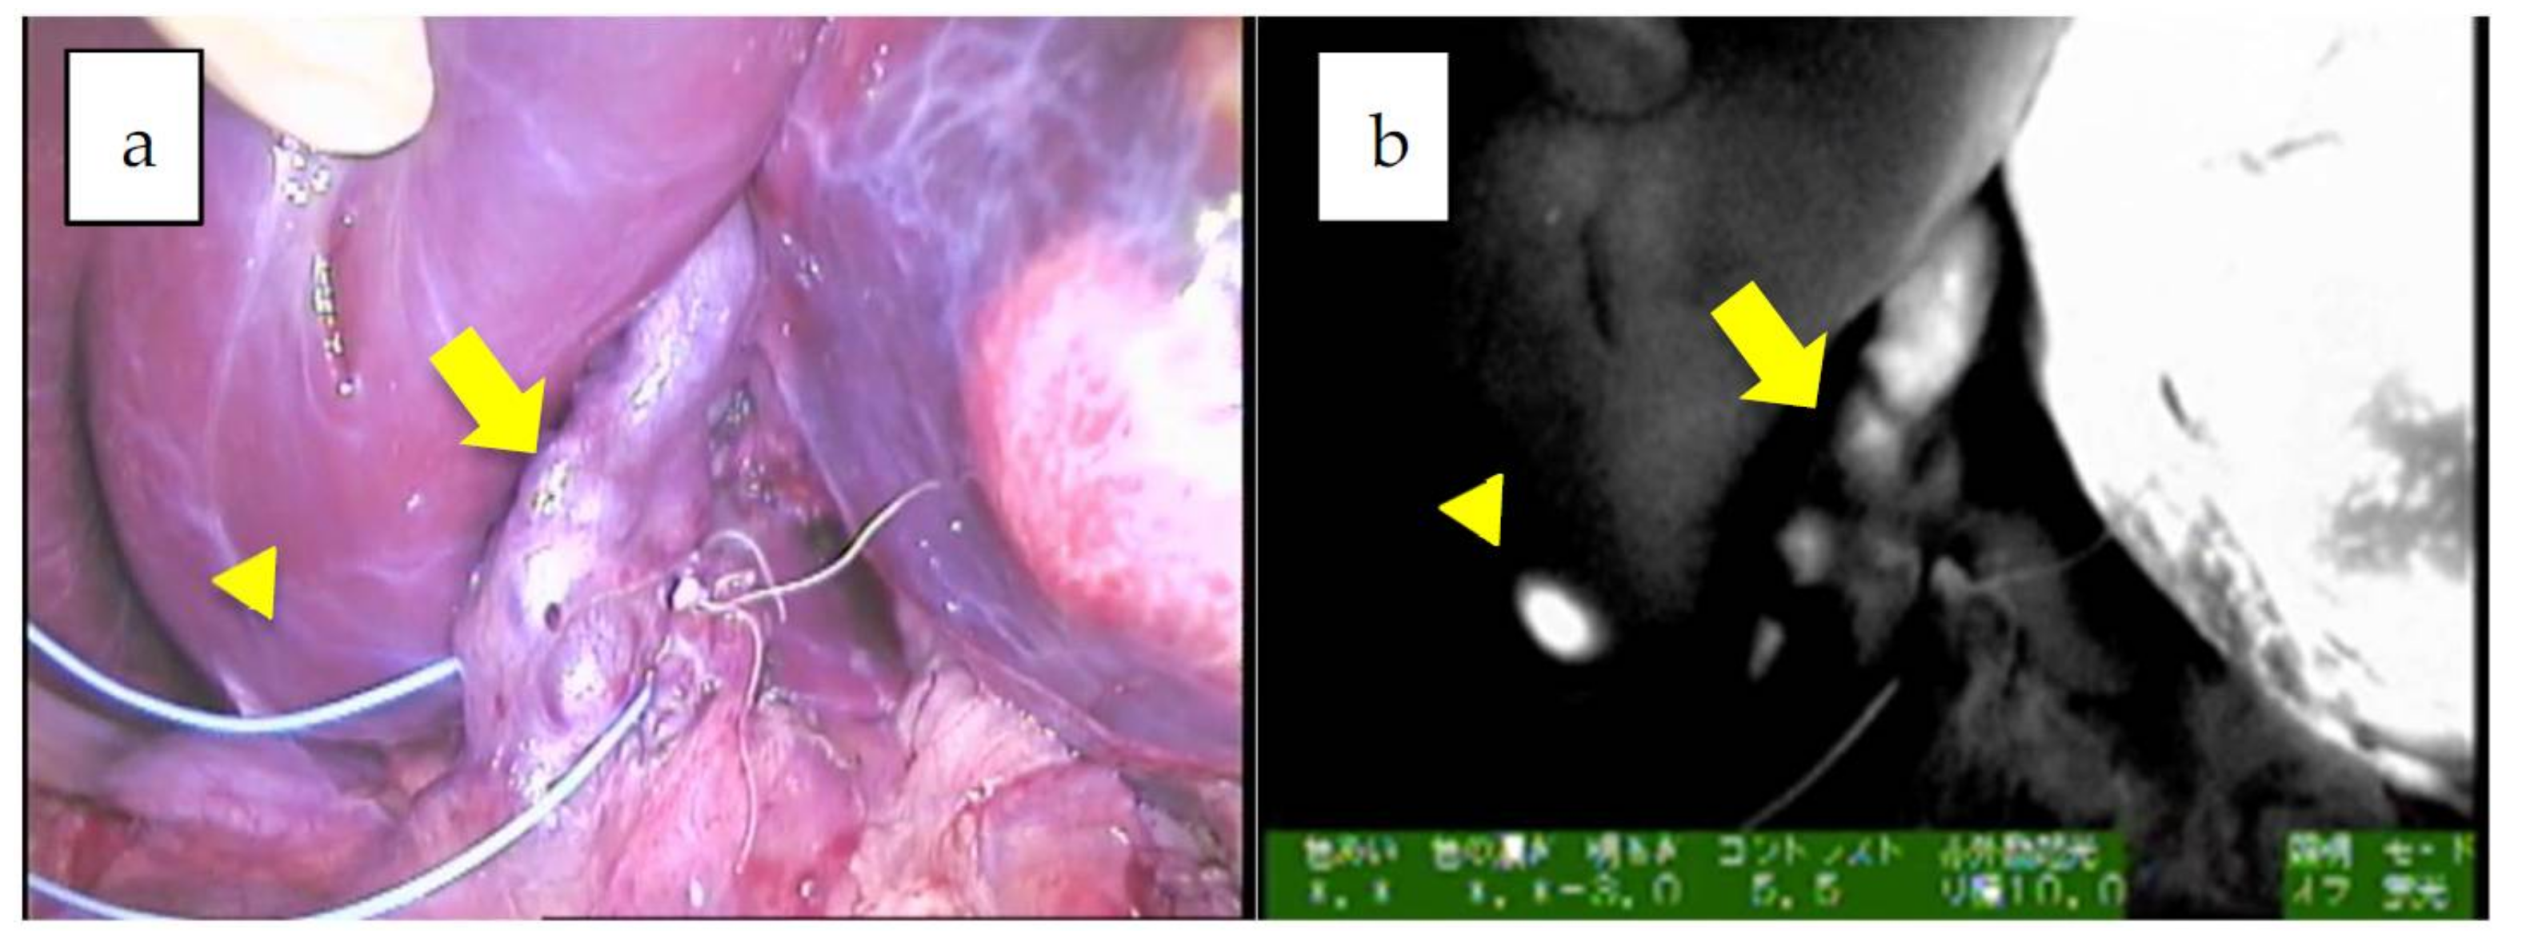

| 4 | 8 | 14y/M | PDE neo system | Resection for peritoneal nodules | wholly epithelial type and fetal subtype | diffuse | undetected | 69 | identification, 34 m |

| 5 | 15 | 7y/M | PDE neo system | Resection for peritoneal nodules | NA | diffuse | 21 × 14 × 18 mm | 525.6 | identification, tumor margin, not disease free |

| 6 | 20 | 19y/F | Pinpoint + PDE neo | Pleural and diaphragm resection | wholly epithelial type and fetal subtype | diffuse | 47 × 38 × 21 mm | 2885 | tumor margin, identification, 28 m |